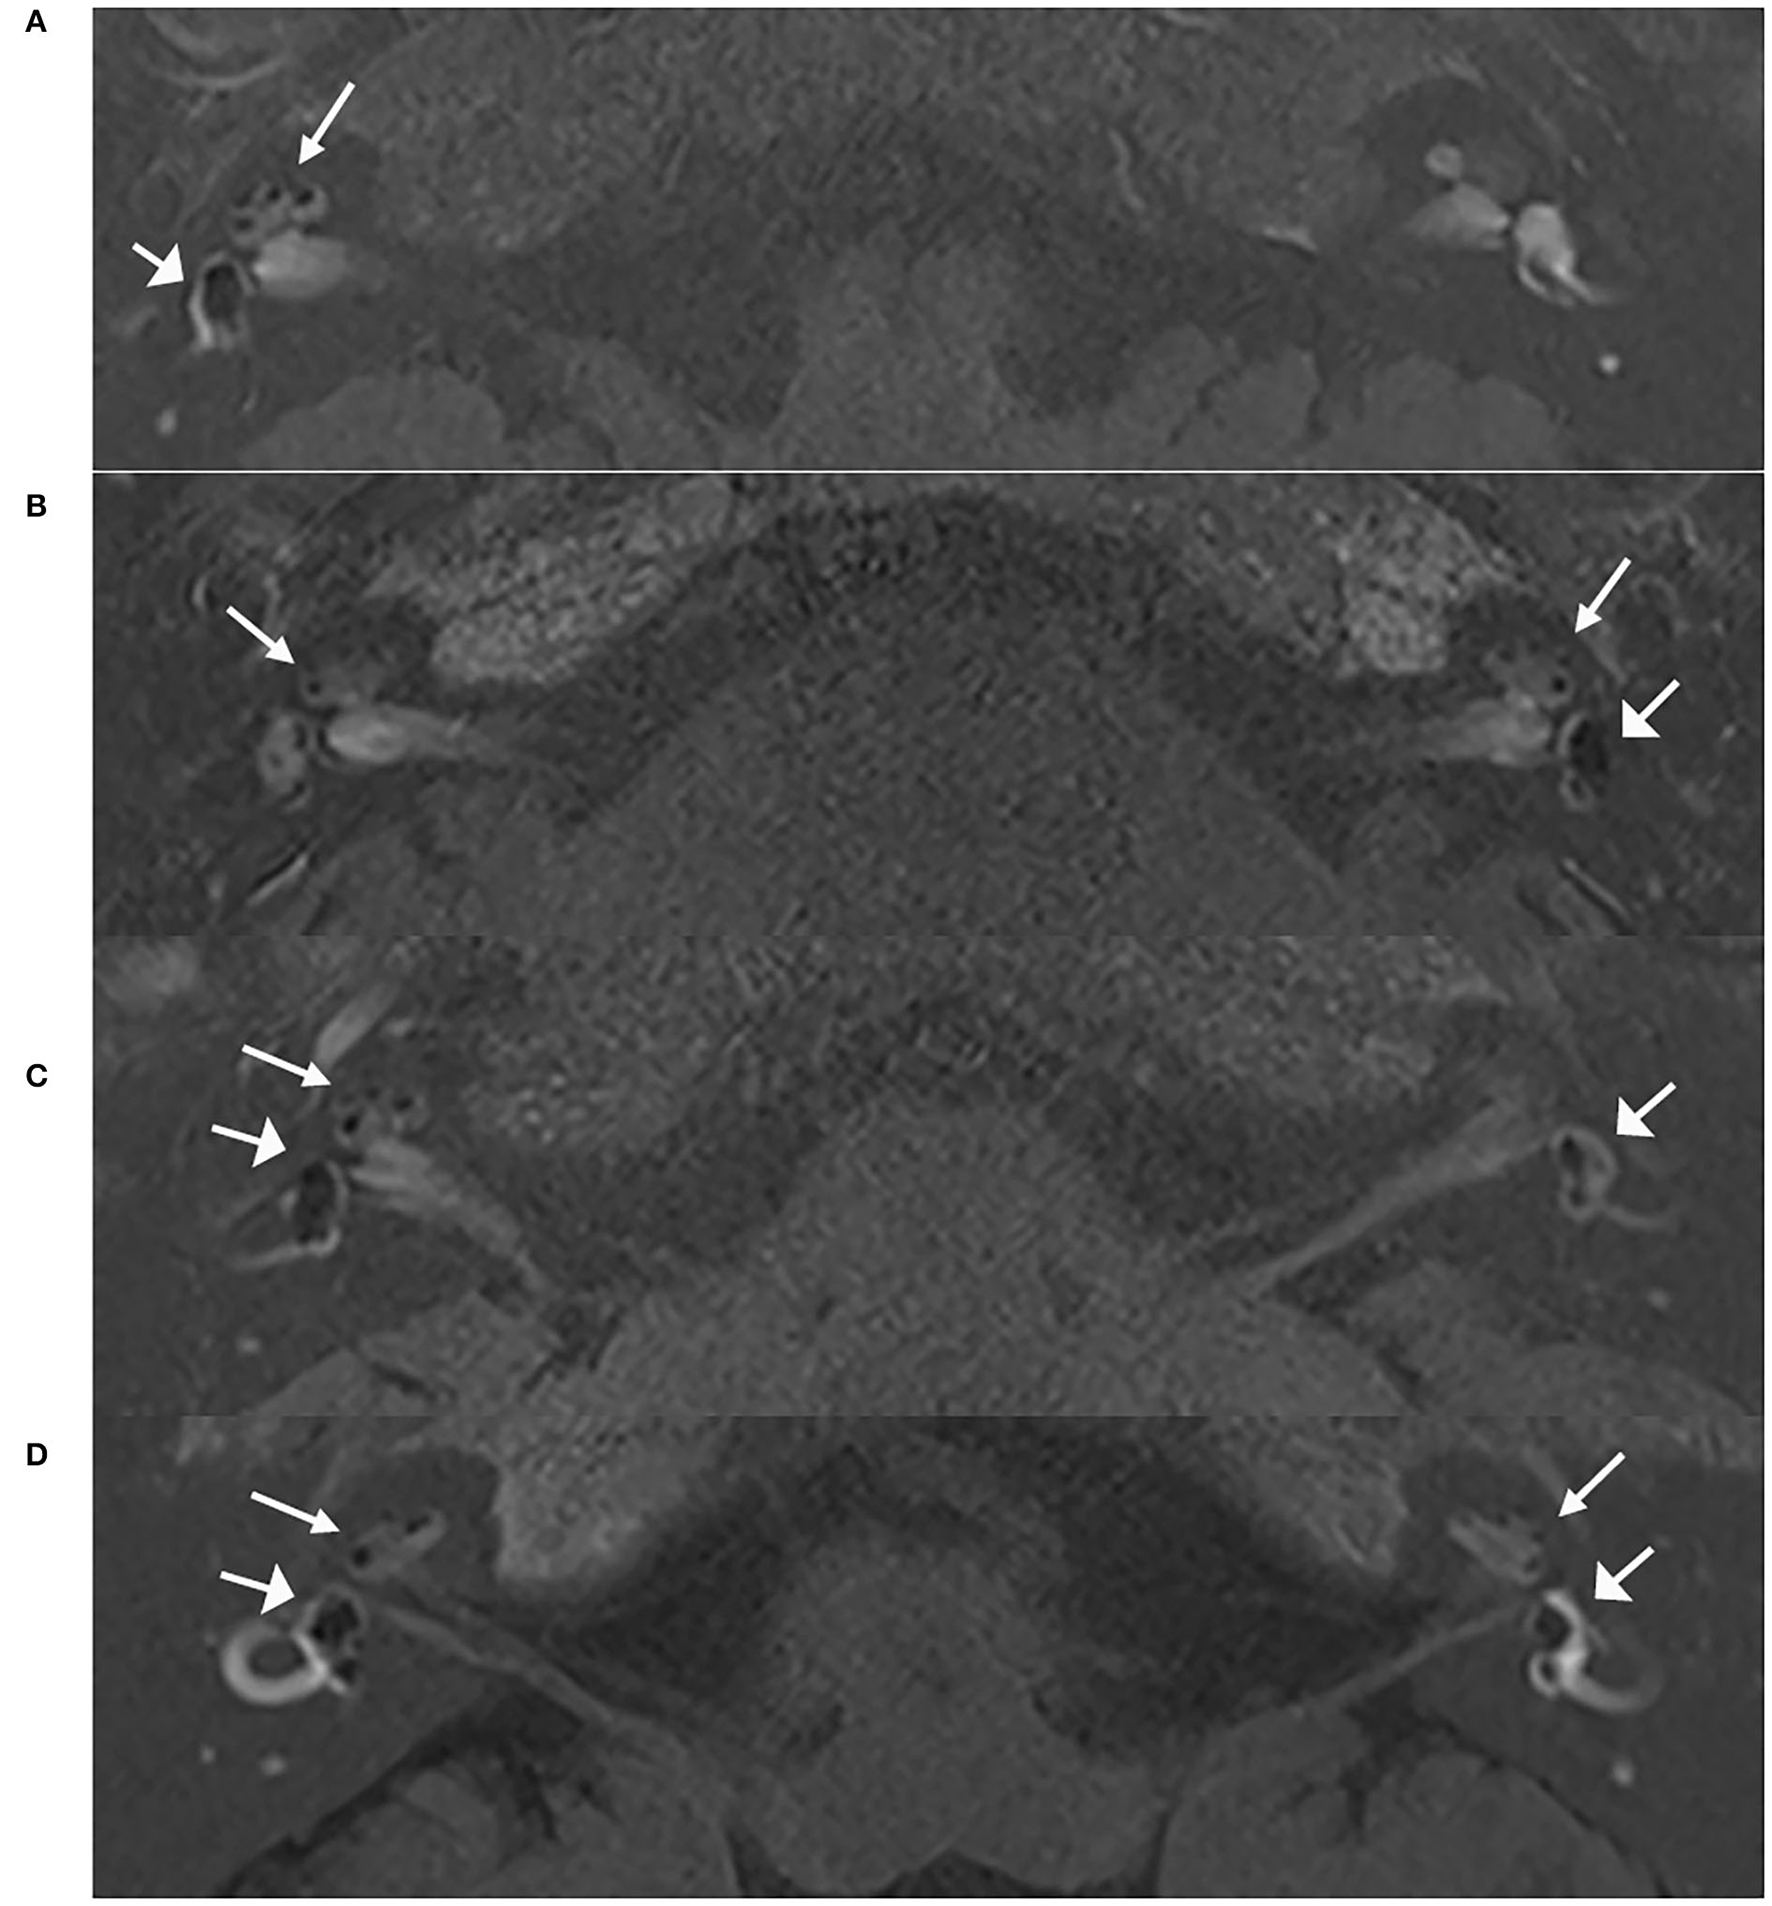

All patients (n = 545, 100%) had EH in the affected ears, including 461 cases with unilateral MD and 84 cases with bilateral MD. Among these 461 patients with UMD, 21 patients (4.6%) had EH on the contralateral side, including 11 patients with only cochlear EH, 3 patients with only vestibular EH, and 7 patients with both cochlear and vestibular EH. The extent of EH on the contralateral side was mild (Figure 1). Of the 21 cases, 9 cases had unexplained hearing loss. Notably, all ears with symptoms of hearing loss, aural fullness, or tinnitus were regarded as symptomatic. For the 84 cases with bilateral MD, all ears (168 ears) had EH, and the proportion of EH in the second involved ear of patients with BMD was significantly larger than that in the contralateral side of patients in the UMD group (P < 0.05) (Table 3).

Figure 1

MRI scans of patients with unilateral and bilateral ELH. Images of 3D real IR performed 4 h after intravenous Gd injection. (A) Vestibular and cochlear ELH on the right side in a patient with unilateral MD; (B) Vestibular and cochlear ELH on the left side and cochlear ELH on the contralateral side in a patient with unilateral MD; (C) Vestibular and cochlear ELH on the right side and vestibular ELH on the contralateral side in a patient with unilateral MD; (D) Vestibular and cochlear ELH on the bilateral ears in a patient with bilateral MD. MD, Ménière's disease. Cochlea (thin arrows) and vestibule (broad arrows).